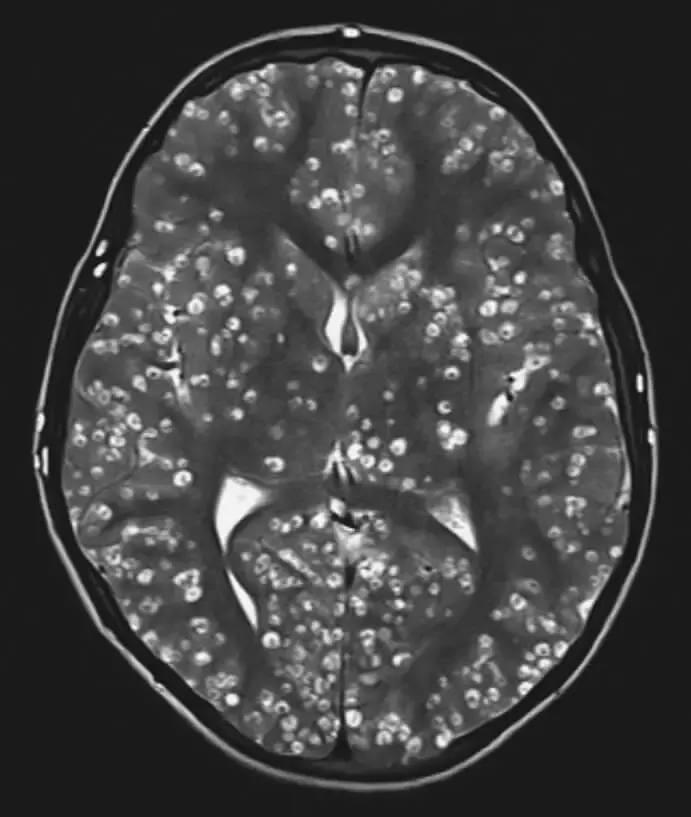

Doctors ran an MRI scan to determine the extent of the damage.

The negative impact that the parasites had on the man’s brain is consistent with a condition known as neurocysticercosis.

Neurocysticercosis happens when parasitic larvae make their way into the brain after a person consumes under-cooked cuts of pork.

After analyzing the MRI scans, the doctors realized that the condition was much worse than they had thought originally.

The man was suffering from several cysts growing on his cerebral cortex.